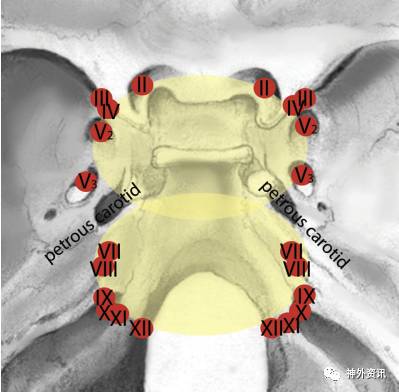

手术并发症中,53.1%患者新发永久性颅神经病变,但均在可耐受范围内;颅神经症状多发生于侧方入路或联合入路。该症状与在岩斜区穿行颅底裂孔的神经和动脉解剖相关(图2)。无论选择何种入路,第Ⅵ颅神经受累最常见。脑脊液漏发生率为28.1%,常出现在内镜下经鼻蝶入路,其次是侧方入路;二者联合入路中脑脊液漏的发生率很低。

图2. 岩斜区颅底裂孔与颅神经、颈内动脉解剖示意图。